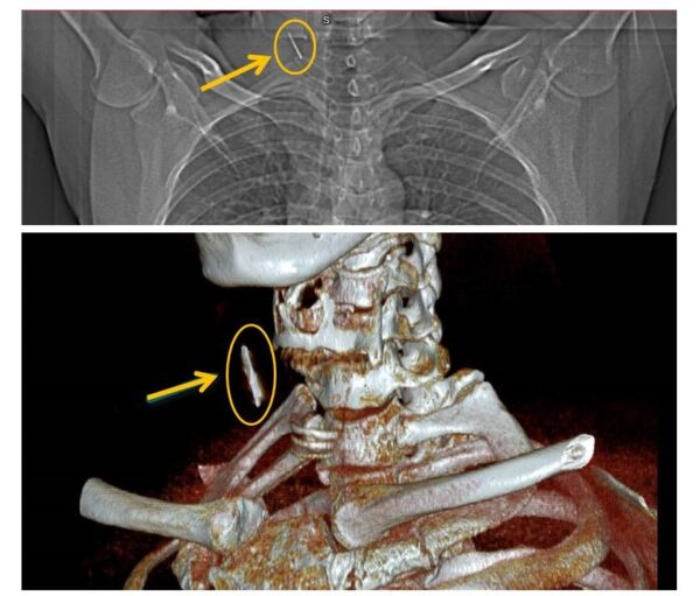

Mr. T.H.C., a 43-year-old resident of Thuy Van, Viet Tri, Phu Tho Province received the shocking news during a health check at Phu Tho General Hospital. An X-ray indicated a potential foreign object deep in his right neck, prompting an ENT specialist to order a CT scan. The scan confirmed the presence of a soft tissue foreign object in the neck.

On June 24, surgeons successfully removed the rusty nail, which was surrounded by fibrous tissue and measured about 2.5 cm. The patient’s condition was stable post-surgery, and he was expected to be discharged within a few days.